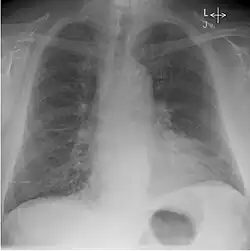

Whilst working at Westminster and the Royal Chest Hospital, Kerley published on the X-ray features of early Pulmonary tuberculosis. As well as his 'B lines' in congestive heart failure he also reviewed X-ray changes in congenital lung diseases, congenital heart disease, intrathoracic aneurysm and bronchiectasis. He gave one of the earliest accounts of chest X-ray and contrast, that is bronchography and lipiodol.[3]

He discovered several of the medical signs used in interpreting radiographs. Famous for his 'B' lines, Kerley B lines are a finding of congestive heart failure.[3] These are short parallel lines perpendicular to the lateral lung surface, indicative of increased opacity in the pulmonary septa. Kerley A lines and Kerley C lines are related findings.[1]